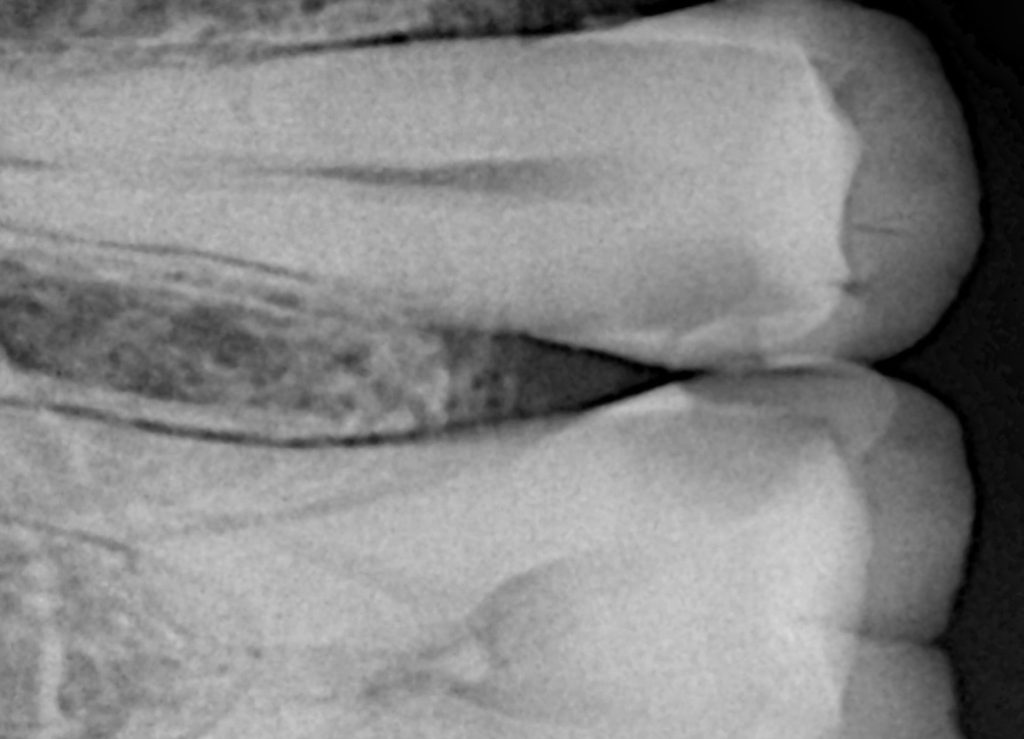

Clinical examination revealed a proximal carious lesion affecting a vital posterior tooth. Pulp vitality tests were positive, and no signs of irreversible pulpal pathology were present. Radiographic assessment confirmed caries limited to dentin without pulpal involvement.

Restoring a Class II cavity is not simply about filling a defect; it is about re-establishing proximal anatomy, contact integrity, and occlusal harmony while preserving pulpal vitality. This case demonstrates a protocol-driven Class II composite restoration performed under absolute rubber dam isolation, using controlled caries removal and precise matrix management to rebuild natural proximal contour and contact predictably.